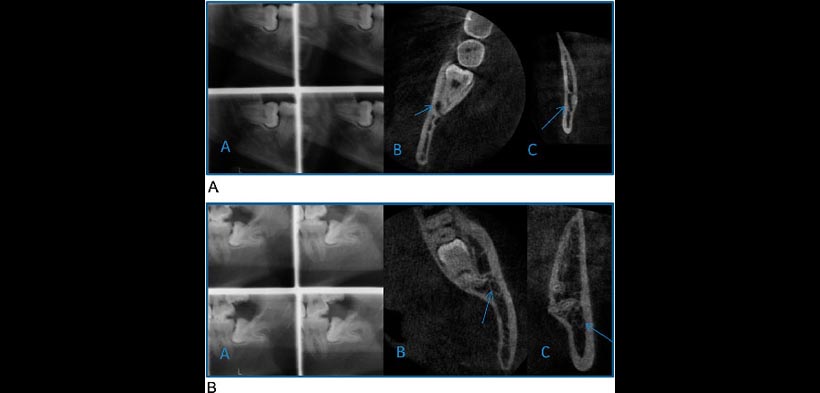

Figura 2 (A) Ejemplo de un tercer molar mandibular derecho en el cual el tratamiento se cambió de la extirpación quirúrgica a coronectomía después de las imágenes de la CBC. A) estéreo escanograma; B) CBCT vista axial; C) CBCT vista coronal. Las flechas indican el canal mandibular. (B) Ejemplo de un tercer molar inferior izquierdo en el cual el tratamiento se cambió de coronectomía a la extirpación quirúrgica después de las imágenes de la CBCT. A) estéreo escanograma; B) CBCT vista axial; C) CBCT vista coronal. Las flechas indican el canal mandibular.